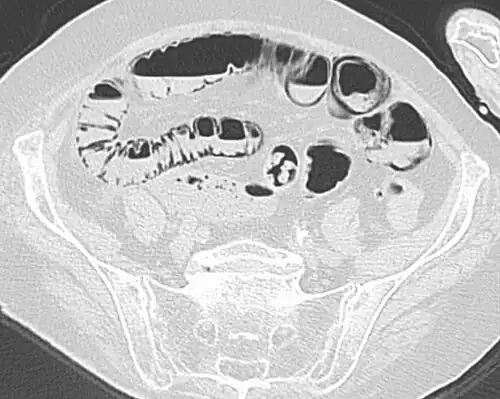

Pneumatosis intestinalis in computed tomography with intestinal ischemia. Lung window for better representation of the gas deposits in the intestinal walls. -

Coronal reformatted MDCT image showing extensive pneumatosis intestinalis in the left upper quadrant small bowel. The pneumatosis is more cystic and nodular in the small bowel in the midline and the right of midline. This patient had a relatively benign presentation without bowel ischemia and was treated conservatively.